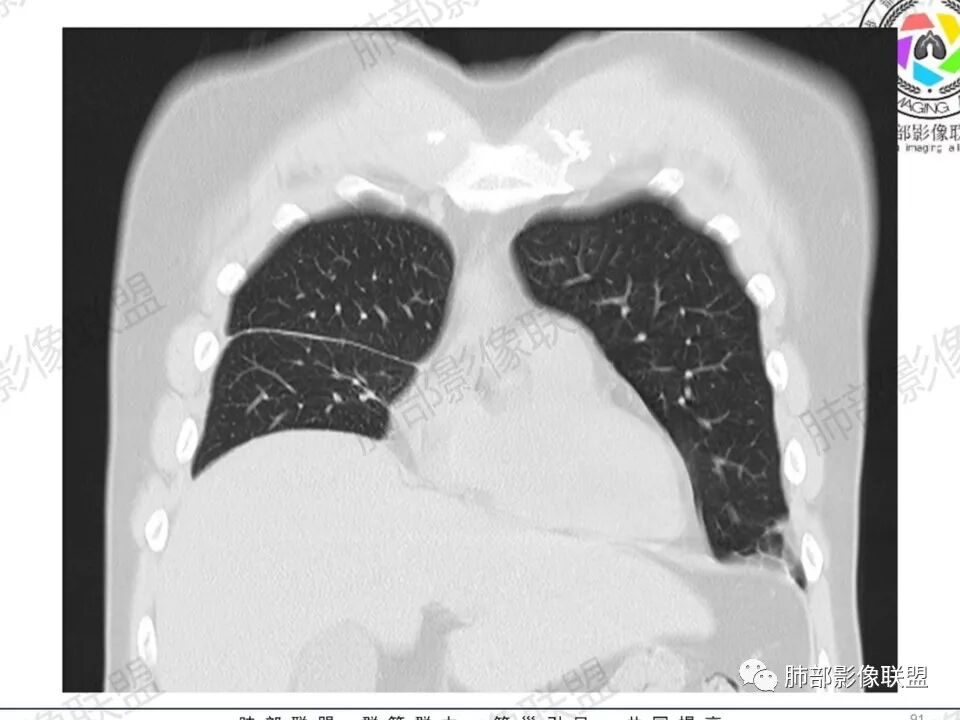

双肺多发结节,胸膜下为主,部分可见空洞。左肺上叶尖后段结节较大,分叶毛刺,周围可见长条索及小斑片影,内空洞比较光滑,内侧壁可见支气管通过。右肺下叶后基底段不张实变,后侧积液,右侧水平裂积液,右侧膈胸膜纵膈胸膜增厚积液,右侧侧胸膜肥厚,考虑1:一元金葡。2二元:金葡,左肺上叶结核。

尘缘: @赵永兵 内蒙巴市临河妇幼影像科 左上肺也是胸膜下(胸膜顶下)的SPE。

@赵永兵 内蒙巴市临河妇幼影像科 支气管是从旁边经过,所以不是空洞,是胸膜下的脓毒栓。如果是结核空洞,应该与支气管相通(因为结核没有血播感染表现的时候,来源是气道,空洞应该与支气管相通),所以支气管从旁边经过,这病灶又在胸膜下,周围也没有干酪坏死。当然是SPE了。

中年男性,左手中指及胸壁疼痛伴发热来诊,影像见双肺多发结节,胸膜下分布为主,部分结节可见空洞,边缘模糊。左肺上叶尖后段结节较大。右肺下叶后基底段不张实变,右侧叶间裂及右侧胸腔积液,右侧侧胸膜肥厚。考虑金葡菌感染,血播SPE。

胸膜下为主多发结节,边缘光滑

伴随楔形影,支气管壁不增厚

空洞内壁光滑,偏心厚壁空洞,张力高